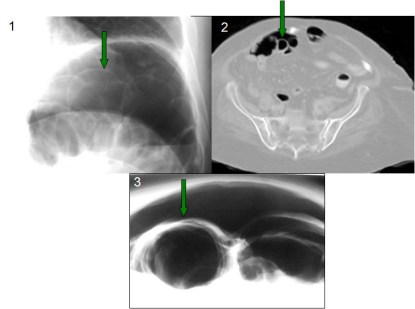

Este signo puede verse también en la radiografía de tórax (1), en la TC (2), y en la placa de abdomen en decúbito supino con rayo horizontal (3) aunque, en general, se requieren cantidades mayores de neumoperitoneo para su demostración.

Localización del ligamento teres (flecha), visible por la presencia de neumoperitoneo. Es visible también el Signo de Rigler.